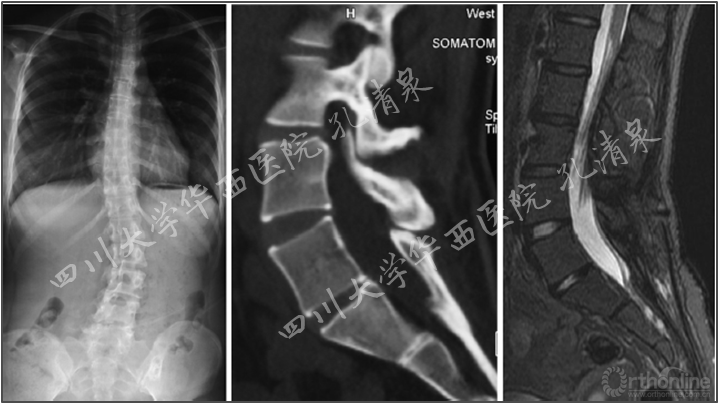

图8 腰椎正位像上示多节段腰椎右侧横突骨折,腰骶部侧凸,CT矢状面重建示腰5椎IV°滑脱,腰5骶1椎间盘完好,骶1前上缘骨骺向前滑移